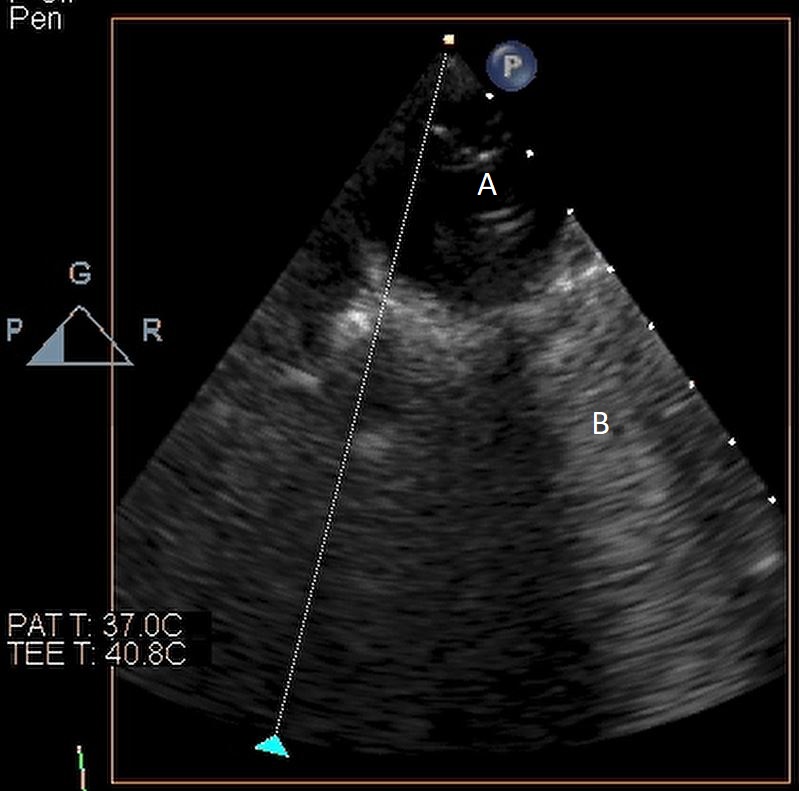

Impella (A) in the LV cavity caused disruption and damage to subvalvular apparatus resulting in flail segment (B) of the mitral valve.

Fig. 4.Impella (A) placement causing disruption and damage to subvalvular apparatus resulting in mitral valve flail (B) and mitral regurgitation (C).